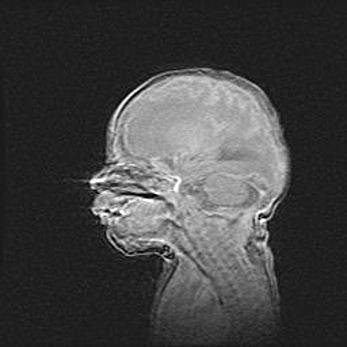

Мальформация Денди-Уокера. Киста задней черепной ямки.

Агенезия мозолистого тела.

Возраст: 2,5 месяца

Вес: 2420 г

Пол: женский

Окружность головы: 37 см

Срок гестации: 32 недели

Мальформация Денди—Уокера — редкий вид патологии ЦНС, представляющий собой врожденный порок развития каудального отдела ствола и червя мозжечка, ведущий к неполному раскрытию срединной (Мажанди) и латеральных (Лушка) апертур IV желудочка мозга. Для этогно синдрома характерна триада симптомов: гипотрофия червя мозжечка и/или полушарий мозжечка, кисты задней черепной ямки, гидроцефалия различной степени. В 70% случаев порок сочетается и с другими аномалиями головного мозга, в частности с агенезией мозолистого тела.